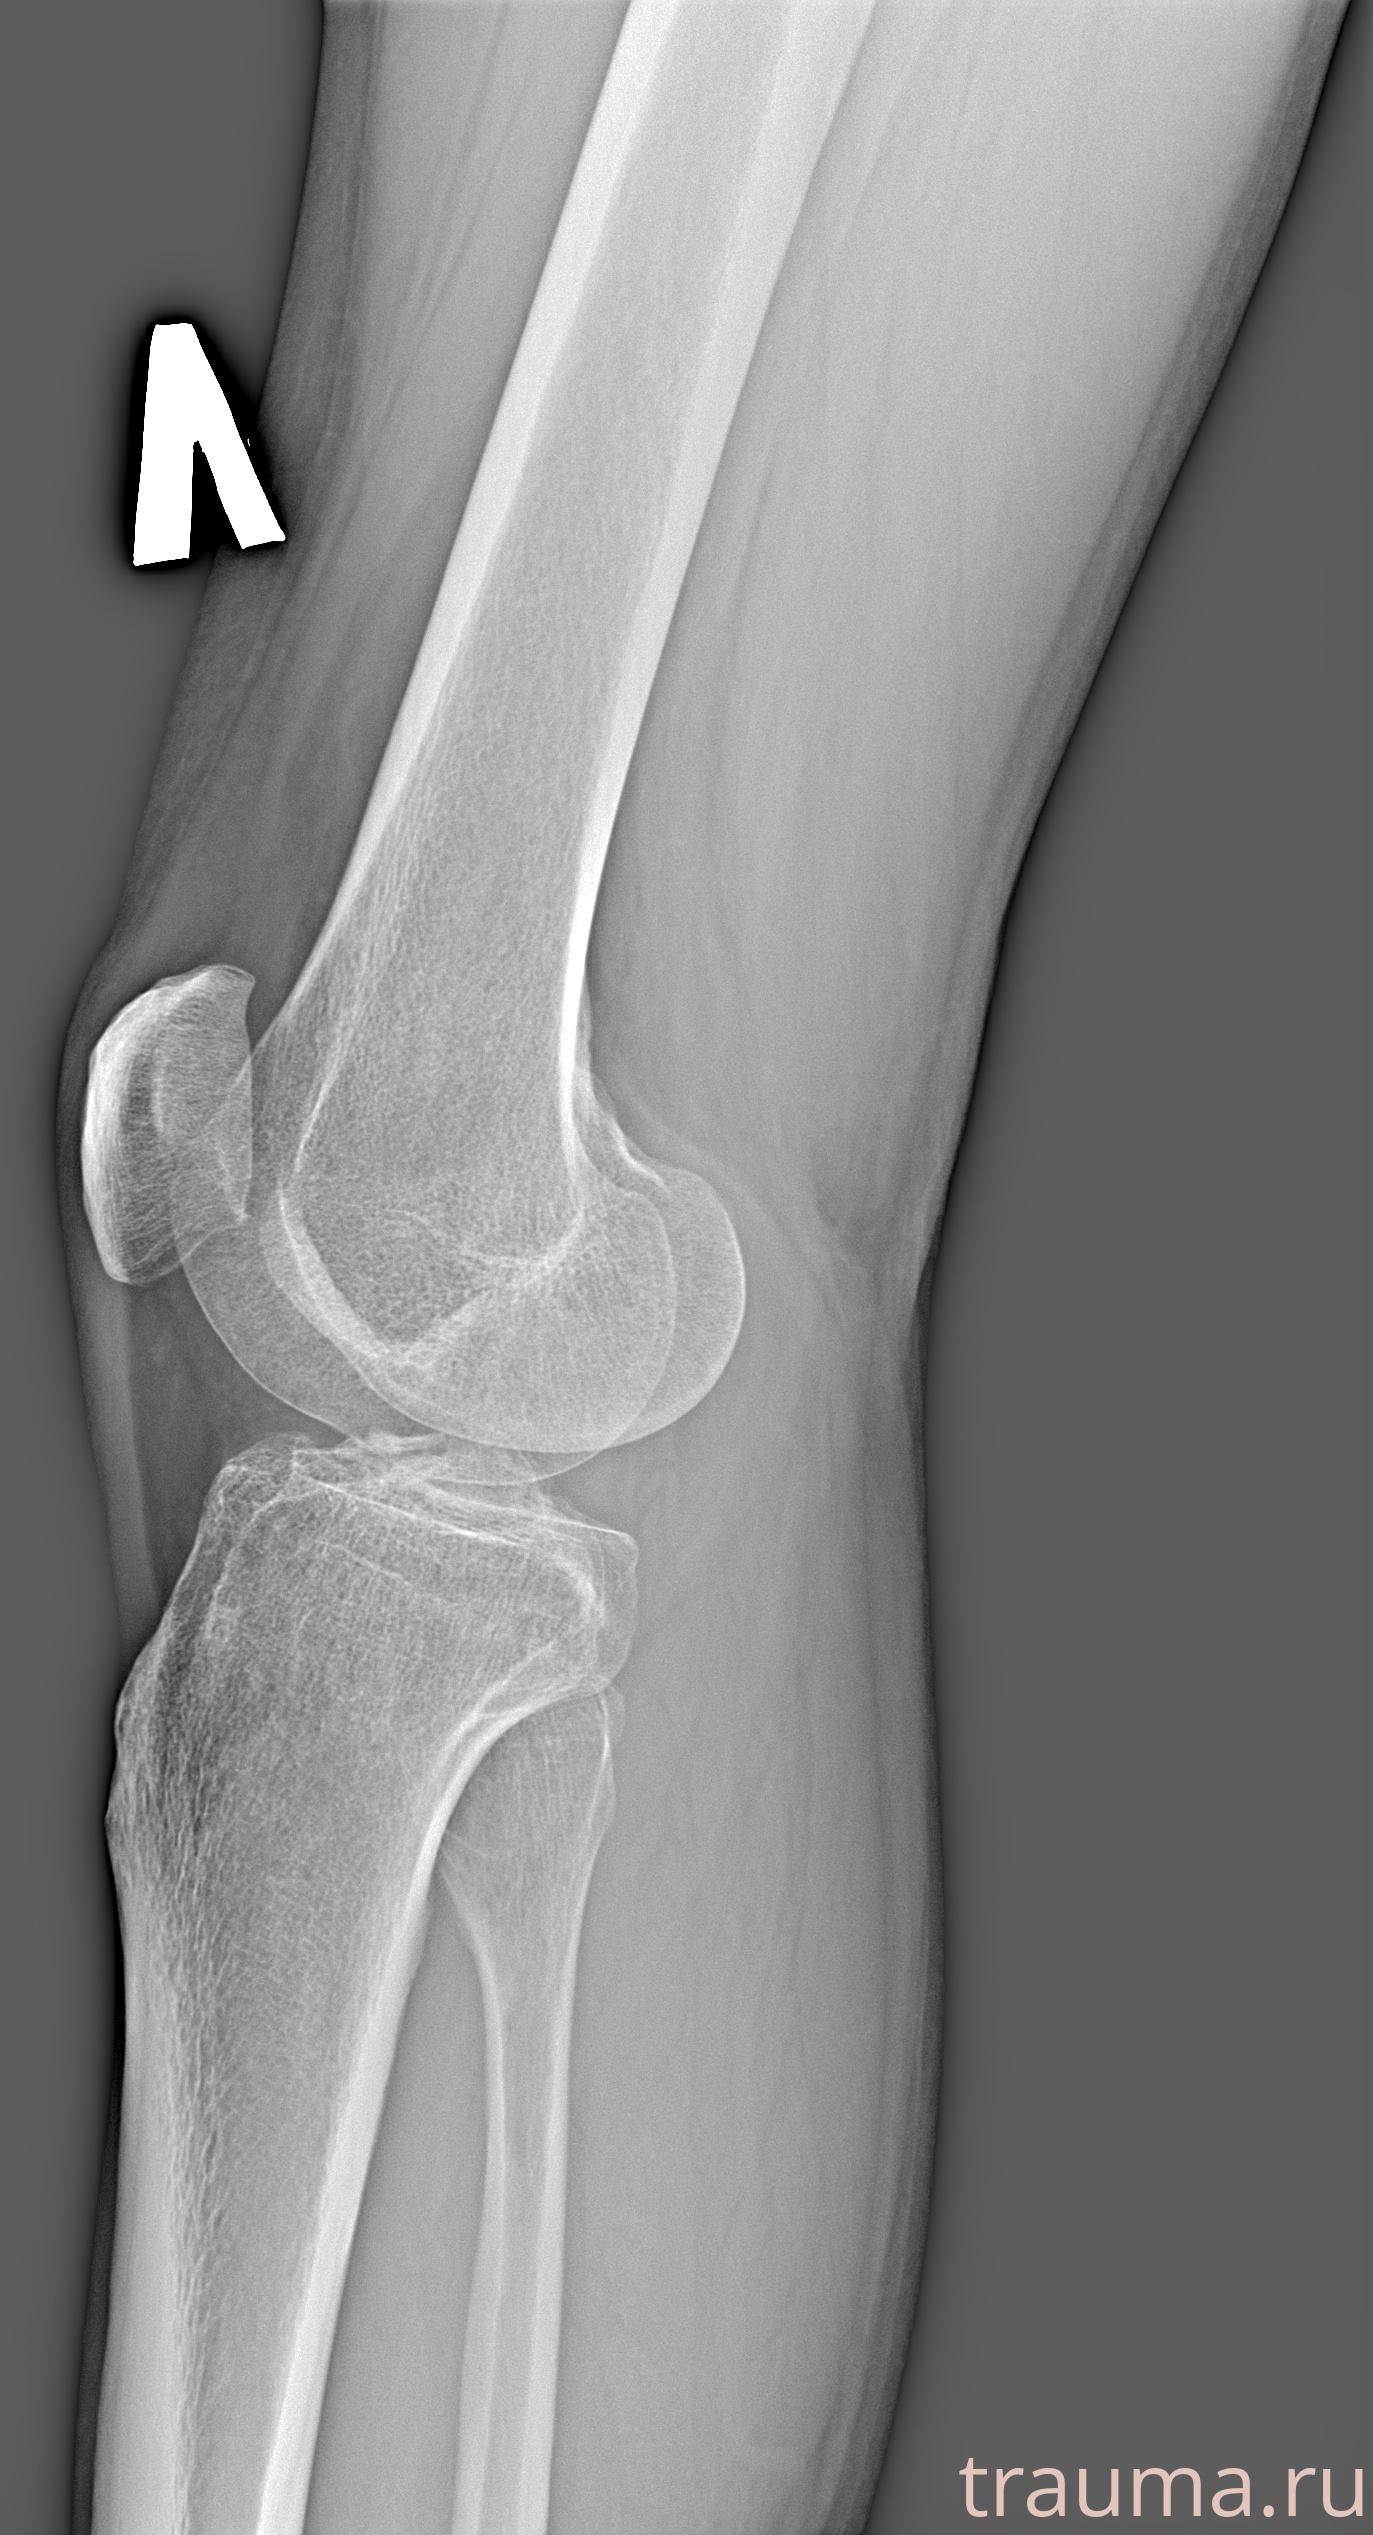

Рентген на дому: по вашему адресу приезжает врач-рентгенолог, травматолог-ортопед с мобильным рентгеновским аппаратом, проводит диагностику травмы или заболевания, делает необходимые рентгенограммы, дает рекомендации по дальнейшему лечению. Получить качественные снимки в домашних условиях возможно благодаря уникальной методике, разработанной МосРентген Центром для института  Склифосовского